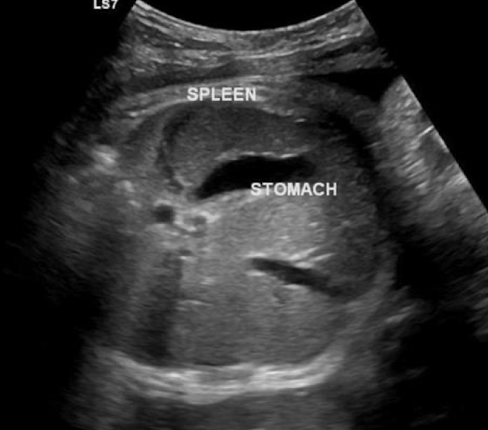

spleen

in LUQ

increases in size during gestation (biggest in 3rd trimester)

best images in TRV plane; to left of stomach

SONO:

homogeneous

similar echogenicity to kidney

less echogenic than liver

stomach

seen by 16w

amniotic, fluid-filled structure